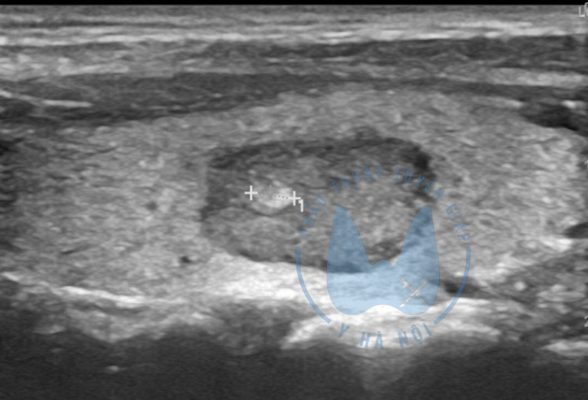

U tuyến giáp lành tính thường phổ biến ở nữ giới, khiến người mắc cảm thấy khó chịu hoặc thậm chí khó thở hay nuốt nghẹn. Để hiểu rõ hơn về quá trình điều trị u tuyến giáp lành tính hiệu quả, cùng MỔ TUYẾN GIÁP theo dõi bài viết...